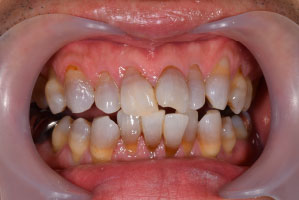

歯列矯正・インレー・クラウン症例

前歯が黒っぽいのが気になる、

悪いところは全部治したい

年齢 54代女性

主訴 歯をきれいにしたい

症例写真(治療前)

担当医師所見

治療前:

八重歯が目立ちます。また銀歯もおおく、見た目が気になります。虫歯も散見できます。